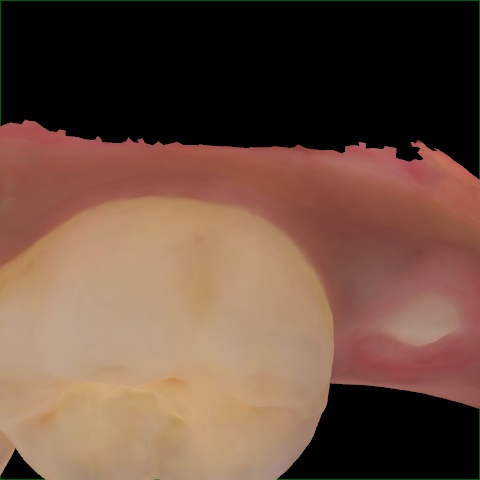

Image 1283 / 1715

NHD35761

Annotated as "Good"

Original Image Rendering Image